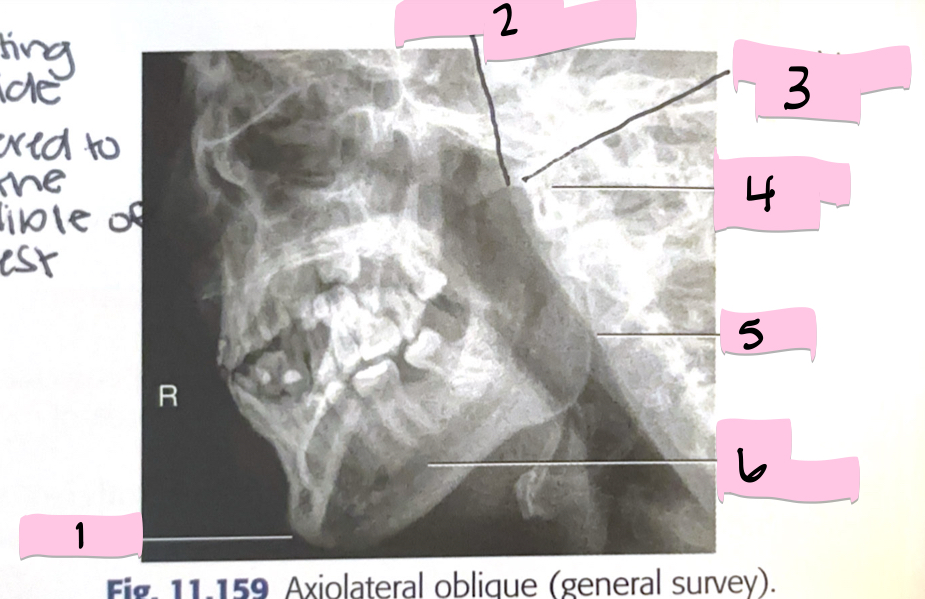

What is 1 pointing to?

Mentum

What is 2 pointing to?

Coranoid process

What is 3 pointing to?

Mandibular notch

What is 4 pointing to?

Condyloid process

What is 5 pointing to?

Ramus

What is 6 pointing to?

Body